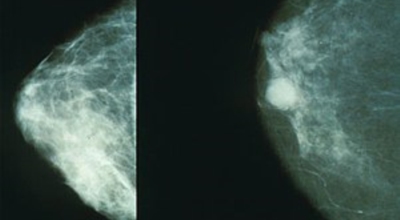

유방암이란?

유방 밖으로 퍼진 악성 종양으로 생명을 위협할 수 있어요. 유방암은 보통 유방의 유관과 소엽에서 생기는데요 남성도 드물게 유방암에 걸릴 수 있어요. 유방암은 아직 명확한 원인이 알려지지 않았어요. 하지만 여러 가지 위험 요인을 추정할 수 있는데요 유전, 호르몬, 노화, 음주, 비만 등이 있답니다. 가장 흔한 증상은 유방에 발생하는 종괴입니다. 그리고 유두 분비, 유방통, 피부궤양, 함몰, 겨드랑이 종괴 등이 나타날 수 있어요. 증상들이 꼭 유방암을 나타내는 것은 아닐 수도 있으므로 정확한 검사가 필요하다고 해요.